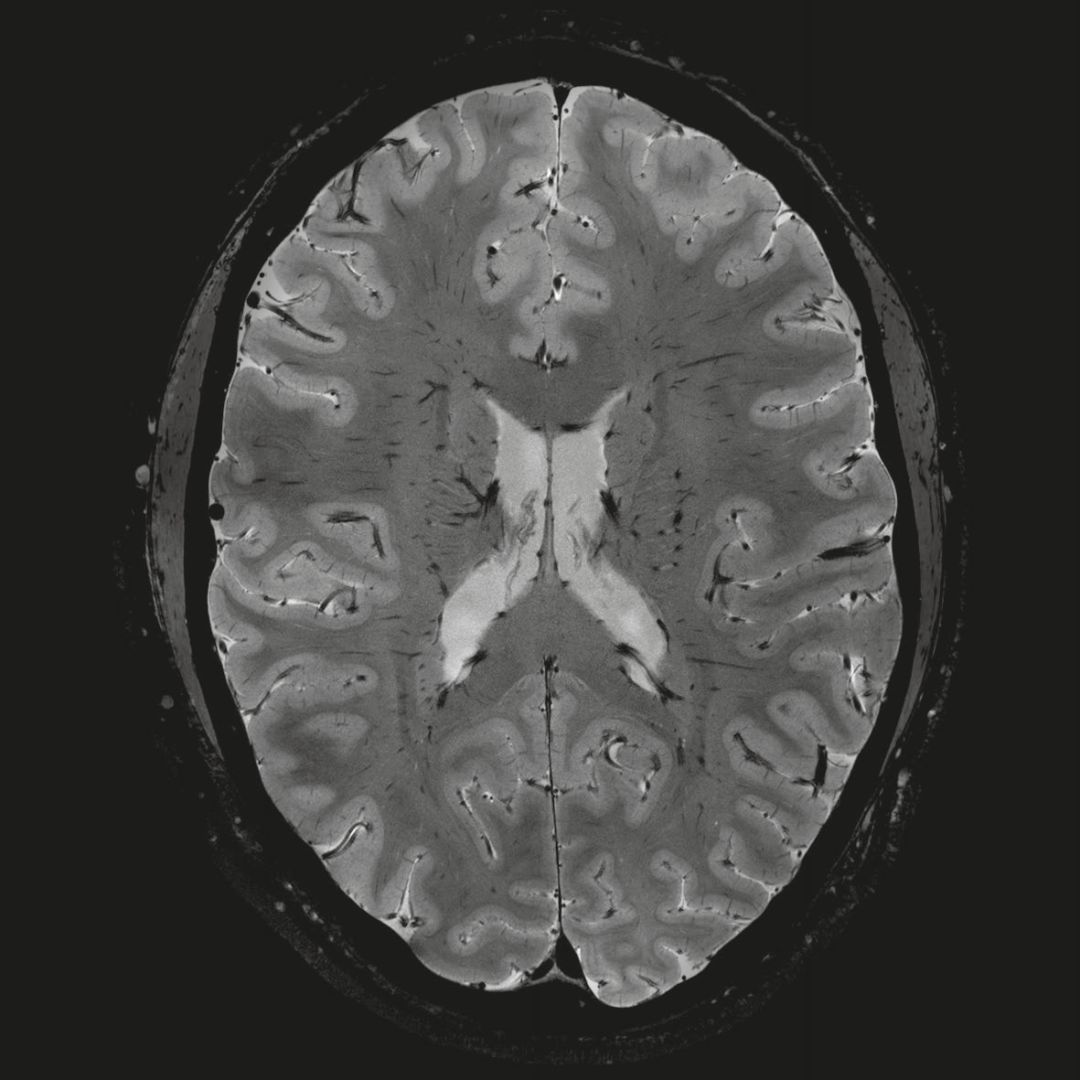

1毫米的各向同性分辨率DTI:神經(jīng)纖維束的交叉細(xì)節(jié)顯示

0.8毫米的各向同性分辨率:精確劃分灰質(zhì)和白質(zhì)

0.8毫米的各向同性分辨率:超精細(xì)的解剖細(xì)節(jié),例:小腦的精細(xì)結(jié)構(gòu)

超精細(xì)的解剖細(xì)節(jié):T2對(duì)比

0.17 x 0.17 x 0.8毫米分辨率超高。

(TOF)300微米的各向同性分辨率顯示最小的血管